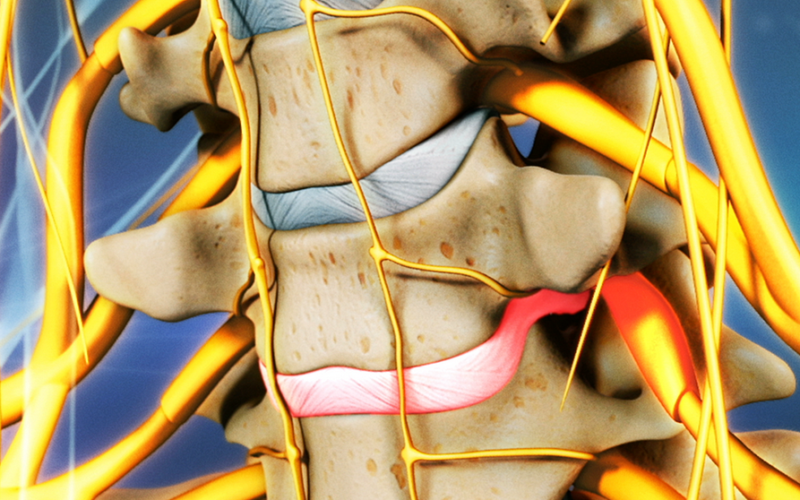

Discectomía endoscópica

Se puede realizar la extracción de una hernia de disco a través de un endoscopio. Se realizar una incisión de 1 cm y se trabaja a través de un canal milimétrico. Así se minimiza el daño a la piel, músculo y hueso, reduciendo al mínimo el sangrado y las cicatrices.

Laminectomía endoscópica

Existe la posibilidad, a través del endoscopio, de aumentar el canal por donde pasan los nervios hacia las piernas (Canal lumbar) en los casos en los que el canal sea demasiado estrecho y genere síntomas como dolor o incapacidad de caminar.